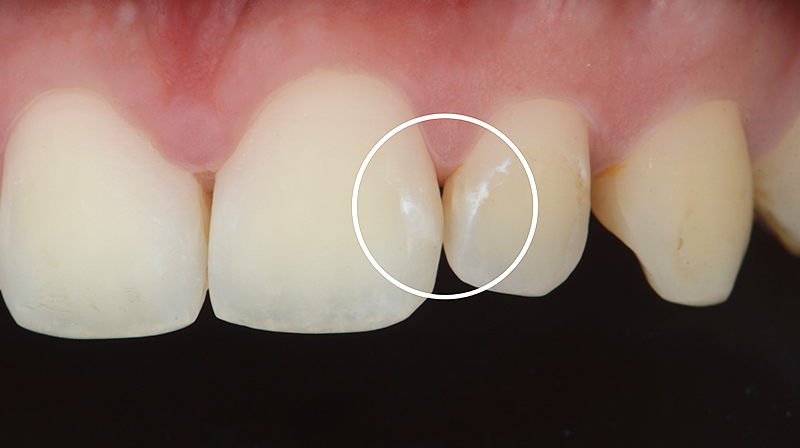

Durante l’esame di routine in un paziente di 25 anni (sottoposto a terapia ortodontica fissa tra gli 11 e 15 anni) vengono rilevate delle ipomineralizzazioni, che si presentano come white spots post-ortodontiche, sugli elementi 21 e 22 (Fig. 5).

Le lesioni sono state trattate in clinica con una singola applicazione di CURODONT™ REPAIR. Al trattamento seguono le istruzioni di igiene ed al paziente viene consegnato un tubetto di CURODONT™ PROTECT da applicare a casa, in piccola quantità, due volte alla settimana sull’area trattata prima del sonno. Sedici mesi dopo il trattamento, alla visita di follow-up, si osserva che clinicamente le white spots non sono più visibili (Fig. 6).

Fig. 5 - White spots postortodontiche, elementi 21 e 22 prima dell’applicazione di CURODONT™ REPAIR (Da: G. Sammarco. Cariologia Clinica. Quintessence publishing Italia, 2025).